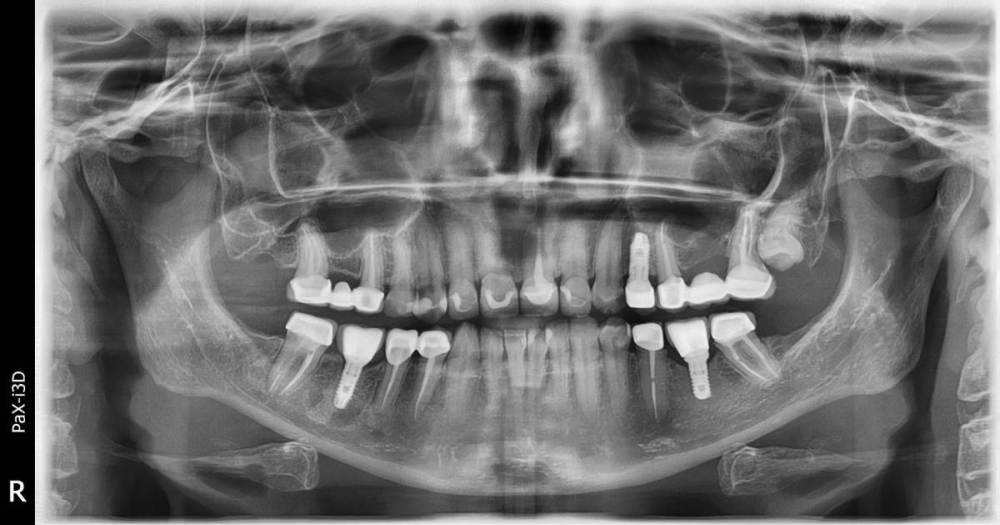

vse32 Опубликовано 7 апреля, 2022 Поделиться Опубликовано 7 апреля, 2022 Здравствуйте коллеги, прошу помощи. Имеем: пациентка 45 лет, заметное увеличение объема в районе угла н.ч. справа. Болей нет, вредных привычек нет, жует на обеих сторонах. Беспокоит только эстетика. При пальпации, как мне кажется, гипертрофия m. masseter справа. Фото и ОПТГ прилагаю. Посоветуйте - нужны ли какие-нибудь еще исследования? Цель - исключить "бяку". Какие есть способы коррекции? Ссылка на комментарий

annda Опубликовано 23 апреля, 2022 Поделиться Опубликовано 23 апреля, 2022 Видно,что прикус снижен.Видно,что бруксизм .Видно,что центр лица смещен,нос через 21й зуб проходит.Видно,что ветви нижней челюсти разные по длине.Видно,что гипертрофия жевательных мышц неравномерная на фоне всего этого.И угол нижней челюсти справа более выражен,куда мышцы крепятся.Как тут асимметрии лица не будет.У Савинова Алексея,царствие небесное, только такие и были на потоке,вот с такой асимметрией. Ссылка на комментарий